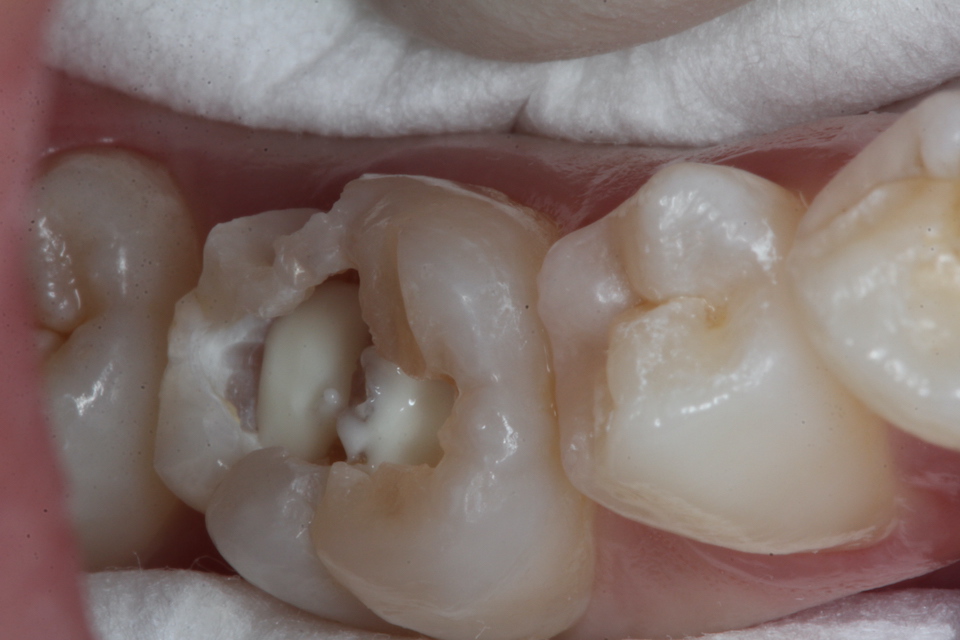

この子は2年後に象牙質の虫歯の進行によりエナメル質が欠けたので再治療した。内部の象牙質がほとんどなくなっているので、過大な咬合力に耐えられない。どうしたものか。。

・・突然歯が欠けたということでやってきた。内部の象牙質は虫歯になっていてプロセスチーズくらいの柔らかさになっていた。多数のクラックが見えると思う。

破折面を見てみると面白いことがわかる。内側から狐色の軟化象牙質(虫歯)、白い脱灰(腐食)が始まっているエナメル質、外側の半透明層が健全なエナメル質だ。なぜこうなるのか?現在の歯科医学の水準では説明が付かない。電気化学的になら説明ができるが、ちょっと眠たくなってきたので、日を改めて。